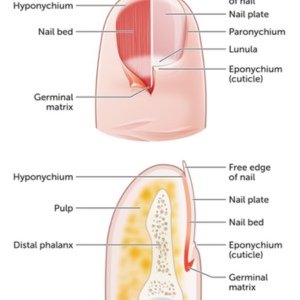

Nail Bed Injuries & Deformities